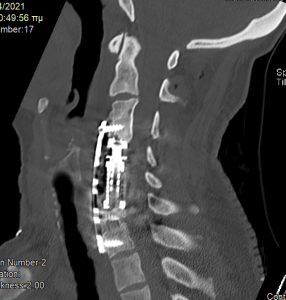

Ο απεικονιστικός έλεγχος με μαγνητική και αξονική τομογραφία της σπονδυλικής στήλης ανέδειξε εικόνα σωματεκτομής Α5, Α6 και μερικώς και Α7. Υπήρχε χαλάρωση των βιδών που καθήλωναν την πλάκα. Συνολικά εικόνα ψευδάρθρωσης και πίεσης επί του νωτιαίου μυελού και των αυχενικών ριζών (κυρίως Α7 δεξιά)

Διενεργήθηκε αρχικά οπίσθια σπονδυλοδεσία με διαυχενικές βίδες Α4, βίδες στα πλάγια ογκώματα Α5 και διαυχενικές βίδες Α7 και Θ1 ενώ έγινε και τρηματεκτομή Α6/7 δεξιά.

Στη συνέχεια, αφαίρεση της πρόσθιας πλάκας, ολοκλήρωση της σωματεκτομής Α5 & Α6, απελευθέρωση του νωτιαίου μυελου, πρόσθια δισκεκτομή Α7/Θ1 και τοποθέτηση πρόσθιας πλάκας Α4-Θ1.

Αρχικά έγινε οπίσθια σπονδυλοδεσία προκειμένω να στηριχθεί ο αυχένας της ασθενούς και να μειωθούν τα άλγη τα οποία οφείλονταν στην “αστάθεια” της αυχενικής μοίρας. Παράλληλα, διενεργήσαμε και οπίσθια τρηματεκτομή ώστε να εξασφαλίσουμε την απελευθέρωση της δεξιάς Α7 ρίζας, η οποία δημιουργούσε πόνο στην ασθενή. Όπως φαίνεται στη μετεγχειρητική αξονική τομογραφία, οι βίδες στους αυχένες του Α4 σπονδύλου τοποθετήθηκαν με ακρίβεια χιλιοστού. Σ’ αυτό, σημαντική ήταν η βοήθεια του διεγχειρητικού νευροπλοηγού σπονδυλικής στήλης με το πιο σύγχρονο σύστημα απεικόνισης (Ο-arm II)

Στη συνέχεια γυρίσαμε την ασθενή σε ύπτια θέση και αφού αφαιρέσαμε την παλαιά πλάκα, αποκαθηλώνοντας τον οισοφάγο, ολοκληρώσαμε τη σωματεκτομή και απελευθερώσαμε τα νευρικά στοιχεία και από μπροστά. Μια και δεν ήταν δυνατή η στήριξη της πλάκας στον Α7, αλλά ούτε και θέλαμε να καταλήξουμε ένα τεράστιο χάσμα, αποφασίσαμε να διατηρήσουμε τον Α7 και να διενεργήσουμε πρόσθια δισκεκτομή Α7/Θ1, καθηλώνοντας τελικά την πλάκα στον Α4, Α7 και Θ1 σπόνδυλο.